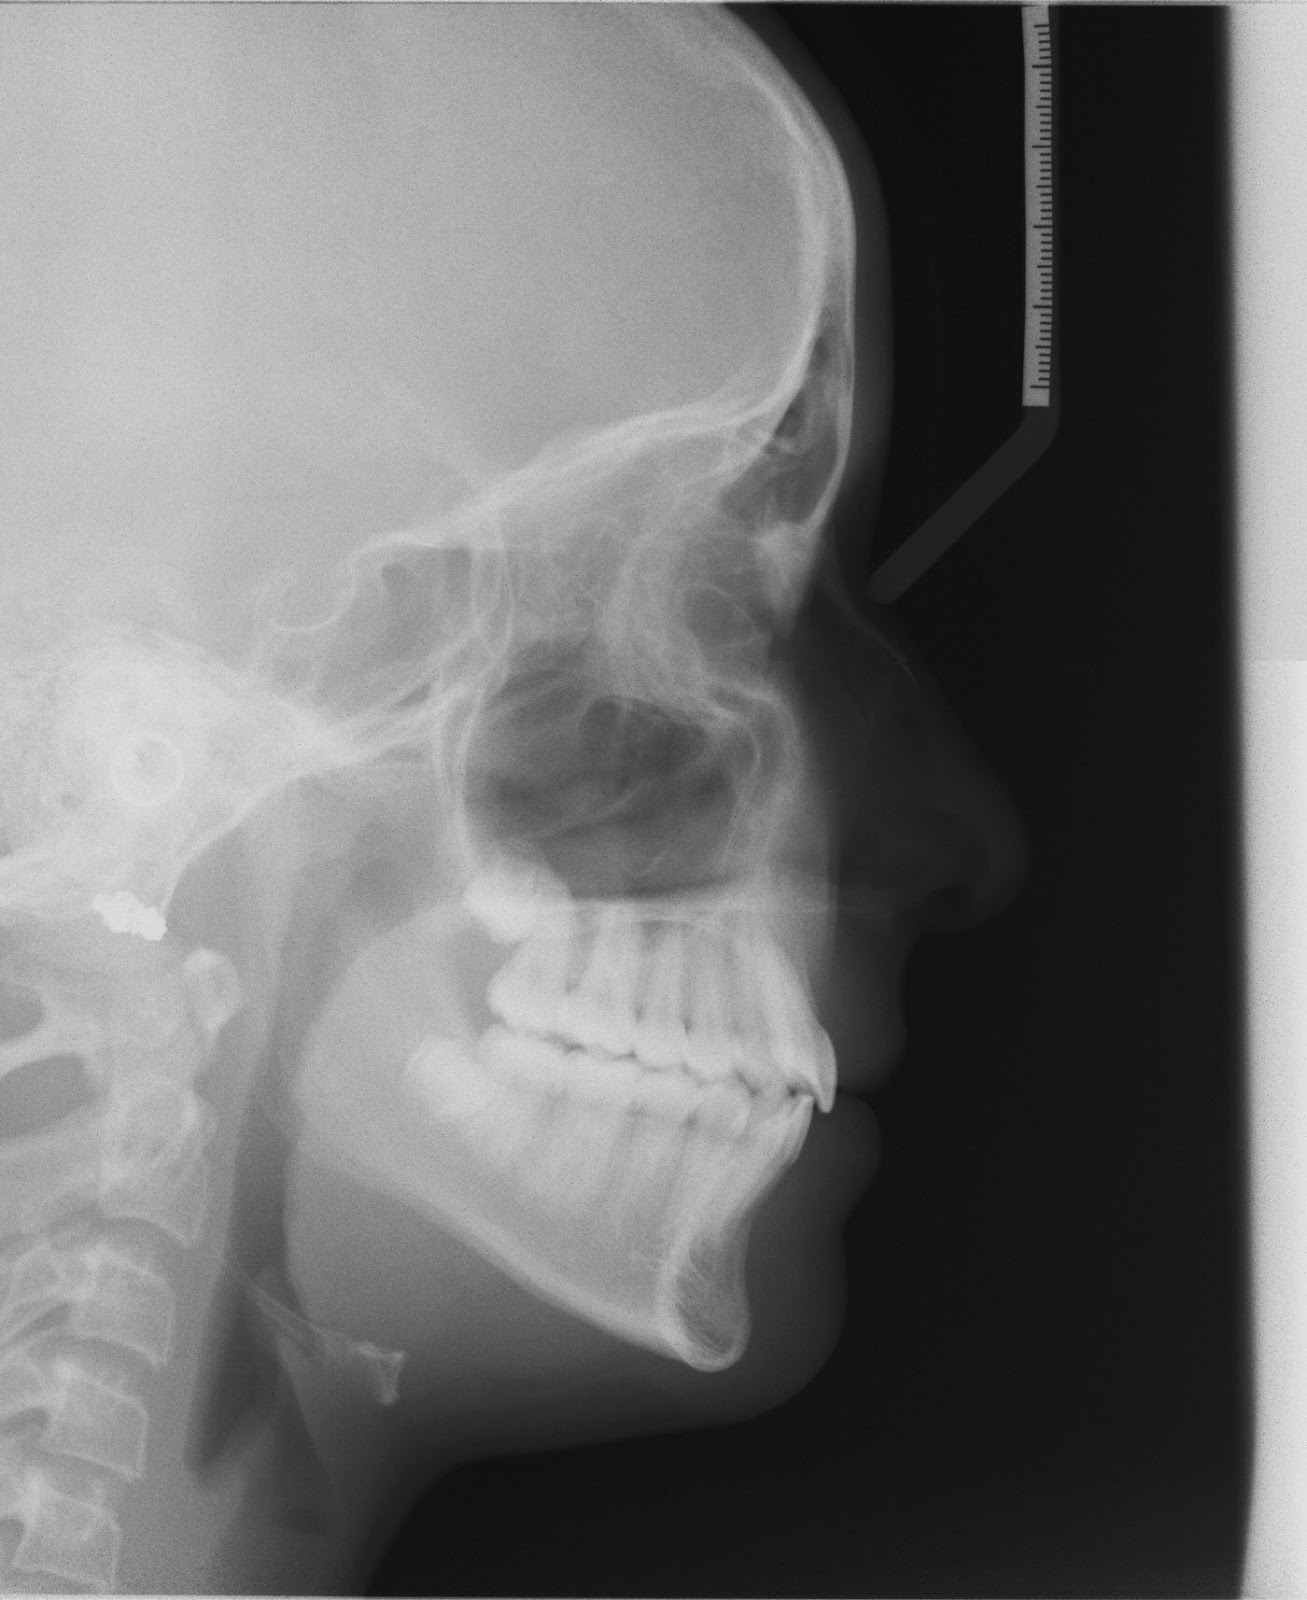

Invisalign is not only a cosmetic solution—it is also an effective treatment for correcting common bite and alignment issues that can impact long-term oral health. Proper alignment helps improve function, reduce uneven wear, and support overall dental stability.

Dr. Haywood uses Invisalign clear aligners to treat mild to moderate orthodontic concerns such as:

- Overbite

- Underbite

- Crossbite

- Open bite

- Tooth crowding and spacing

Using advanced digital planning, Invisalign treatment is customized to guide teeth into optimal position with precision and predictability. Each aligner applies gentle, controlled force to ensure safe, gradual movement over time.